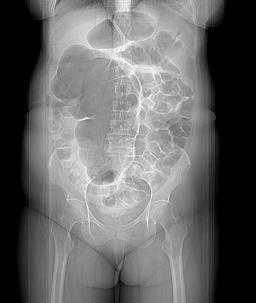

A simple abdominal radiograph is diagnostic of acute sigmoid volvulus in 57% to 90% of cases, presenting with the classic “coffee bean sign.”49,50 (See Figure 3.) These patients will display a dilated sigmoid colon and also may display multiple air-fluid levels within the large and small bowels.42 CT imaging also may be used, with a typical “whirl pattern” in the colon indicating the presence of sigmoid volvulus. (See Figure 4.) CT scans have been reported to be diagnostic in nearly 100% of cases.42

Figure 4. Scout Film from a Computed Tomography of the Abdomen Demonstrating a Dilated Loop of Bowel in the Shape of a Coffee Bean |

Source: Image courtesy of J. Stephan Stapczynski, MD. |